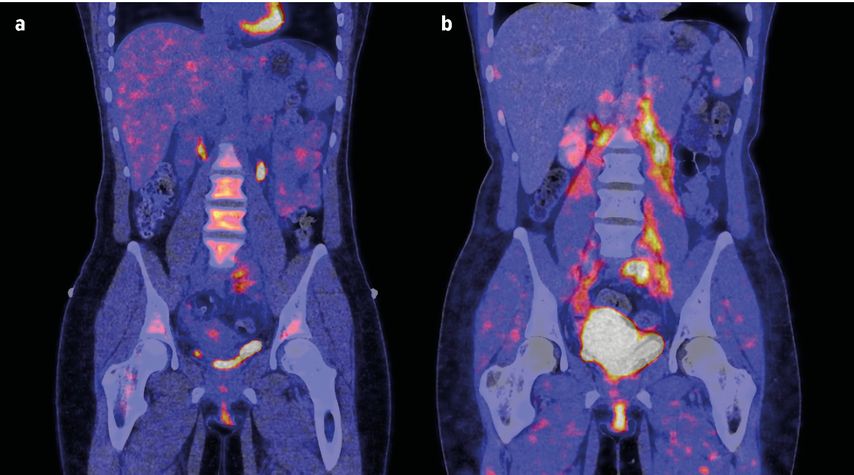

Um die Technologie in dieser Indikation zu validieren, wurde in der Arbeitsgruppe von Ramming eine klinische Querschnittsstudie an einer Kohorte von 27 Patienten mit IgG4-Syndrom durchgeführt.2 Die Probanden wiesen unterschiedliche Grade an entzündlichen, fibrotischen und gemischten Manifestationen auf. Zunächst wurden die Studienteilnehmer einem PET-Scan unterzogen, und zwar einerseits mit einem FAP-spezifischen Tracer (68Ga-FAPI-04) und andererseits mit dem klassischen 18F-FDG-Tracer (zur Visualisierung des Glukosestoffwechsels und damit letztlich des Entzündungsprozesses). Zusätzlich wurden eine MRT und eine Histopathologie gemacht.

Eine wichtige Beobachtung war, dass sich die sehr frühen entzündlichen Stadien von späteren fibrotischen Stadien unterscheiden ließen. Die entzündlichen Frühstadien zeigten starke Signale im FDG-PET, wohingegen kein FAPI-PET-Signal zu sehen war. Umgekehrt zeigten fibrotische Spätstadien der Erkrankung kein Signal im FDG-PET, allerdings eine deutliche Aktivität im FAPI-PET. Eine Korrelation zwischen den beiden Signalen konnte nicht gefunden werden, was die Forschergruppe in der Annahme bestätigte, dass durch den FAPI-PET-Tracer tatsächlich etwas vollkommen anderes als der entzündliche Prozess detektiert wird.

Außerdem wurde in der Studie die Fragestellung adressiert, inwieweit eine immunsuppressive Therapie die mesenchymale Aktivität beeinflussen kann. In einem longitudinalen Ansatz wurden die PET-CT-Daten (18F-FDG- und 68Ga-FAPI-PET-CT) vor und nach einer immunsuppressiven Therapie mit Rituximab ausgewertet und mit den klinischen Befunden sowie den MRT-Daten korreliert. Es zeigte sich, dass die entzündliche Komponente unter Therapie sehr gut unter Kontrolle zu bringen war, während die mesenchymale Aktivität weit schlechter auf die B-Zell-Depletion ansprach. Mehr als 50% der aktiven FAPI-Läsionen waren nach 6-monatiger Behandlung noch nachweisbar. Die persistierende mesenchymale Aktivität war zudem mit einer weiteren Größenzunahme der jeweiligen Weichteilmasse assoziiert (volumetrisch mittels CT gemessen) und korrelierte mit den klinischen Symptomen der Patienten.